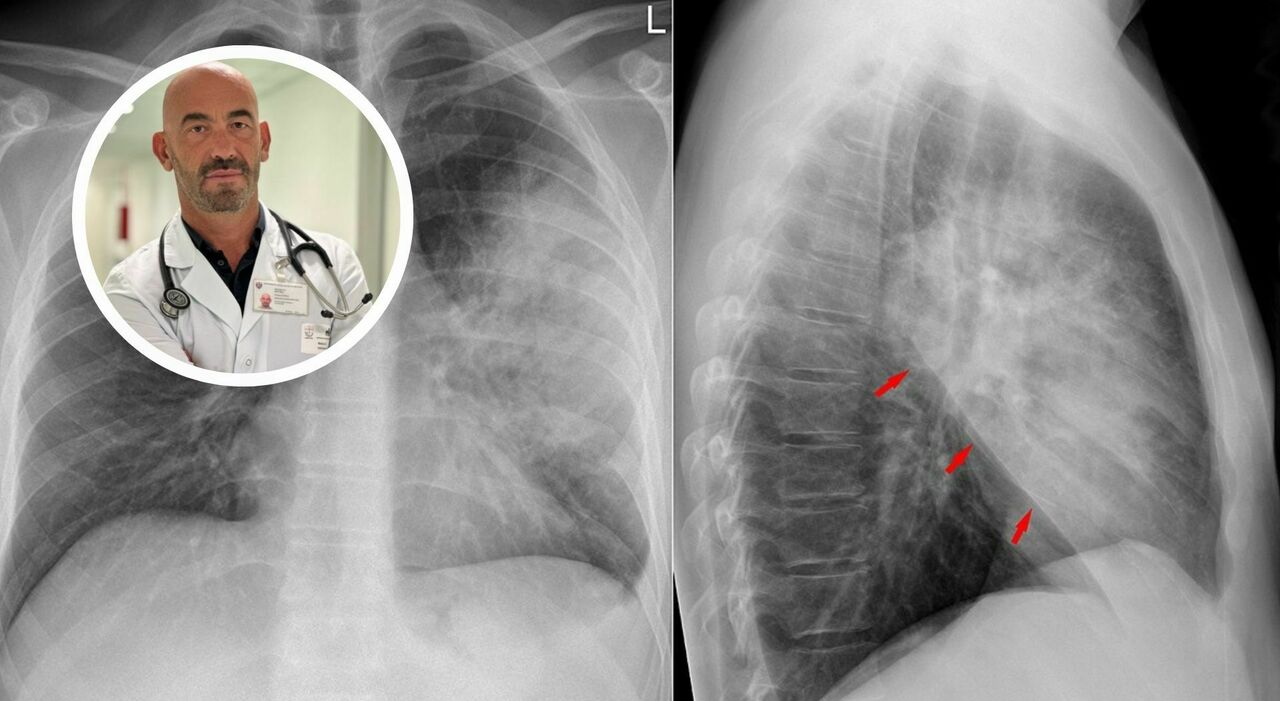

Polmonite, boom di casi. Bassetti: «Ospedali già pieni». Sintomi, cause, cure e cosa non fare - «I nostri ospedali sono già oggi pieni di casi di polmonite», avverte Matteo Bassetti, direttore Malattie infettive dell'ospedale policlinico San Martino di Genova. Scrive msn.com

Polmonite, è boom di casi in tutta Italia. Bassetti: “Non bisogna sottovalutarla, ospedali già pieni” - Matteo Bassetti, adnkronosMatteo Bassetti adnkronos “I nostri reparti ospedalieri stanno già registrando un numero ... msn.com scrive

“Ospedali già pieni!”. Bassetti lancia l’allarme: boom di casi in Italia - «I nostri ospedali sono già oggi pieni di casi di polmonite», avverte Matteo Bassetti, direttore delle Malattie infettive dell’ospedale policlinico San ... Segnala thesocialpost.it